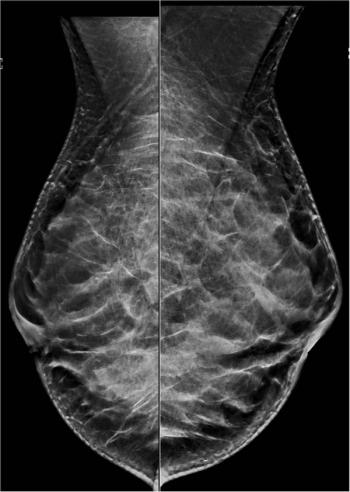

Case History: 49-year-old female presented with palpable right breast retroareolar mass.

Breast images performed outside cancer centers may be interpreted differently if reinterpreted at a cancer center.

47-year-old patient offered screening ultrasound due to dense breast tissue.